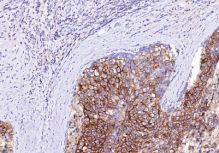

抗原-抗體免疫染色 | 免疫組化 |

|